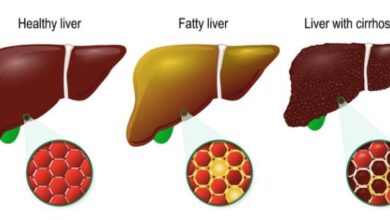

- التهاب الكبد الوبائي “ب” المزمن: في هذه الحالة تستمر مدّة العدوى بالفيروس لفترةٍ قد تتجاوز ستة أشهر، وقد لا يحدث التعافي التام منها بحيث تستمر العدوى لفتراتٍ طويلة وقد تُلازم الشخص مدى الحياة؛ إذ إنّ الجهاز المناعي لا يكون قادرًا على مُحاربتها والقضاء عليها، ومن الجدير ذكره أنّه كلما كان عمر الشخص أصغر عند إصابته بفيروس الكبد الوبائي “ب” ازداد خطر تطوّر النوع المُزمن من هذه العدوى؛ تحديدًا الأطفال ممّن هم أقلّ من 5 أعوام، ومن الجدير ذكره أنّ التهاب الكبد الوبائي “ب” المزمن قد يترتب عليه تطوّر مُضاعفات مُعينة؛ مثل تشمّع الكبد (بالإنجليزية: Cirrhosis)، أو الفشل الكبدي، أو سرطان الكبد، ومن الجدير ذكره أنّ العدوى المزمنة بفيروس الكبد الوبائي “ب” قد تستمر لعقود دون أن يتمّ تشخيصها وقد لا يتمّ الكشف عنها حتّى تتطوّر مضاعفات خطيرة تُشير إلى الإصابة بها، وعليه فإنّ التشخيص والعلاج المُبكر يلعبان دورًا في التقليل من احتمالية تطوّر المُضاعفات.